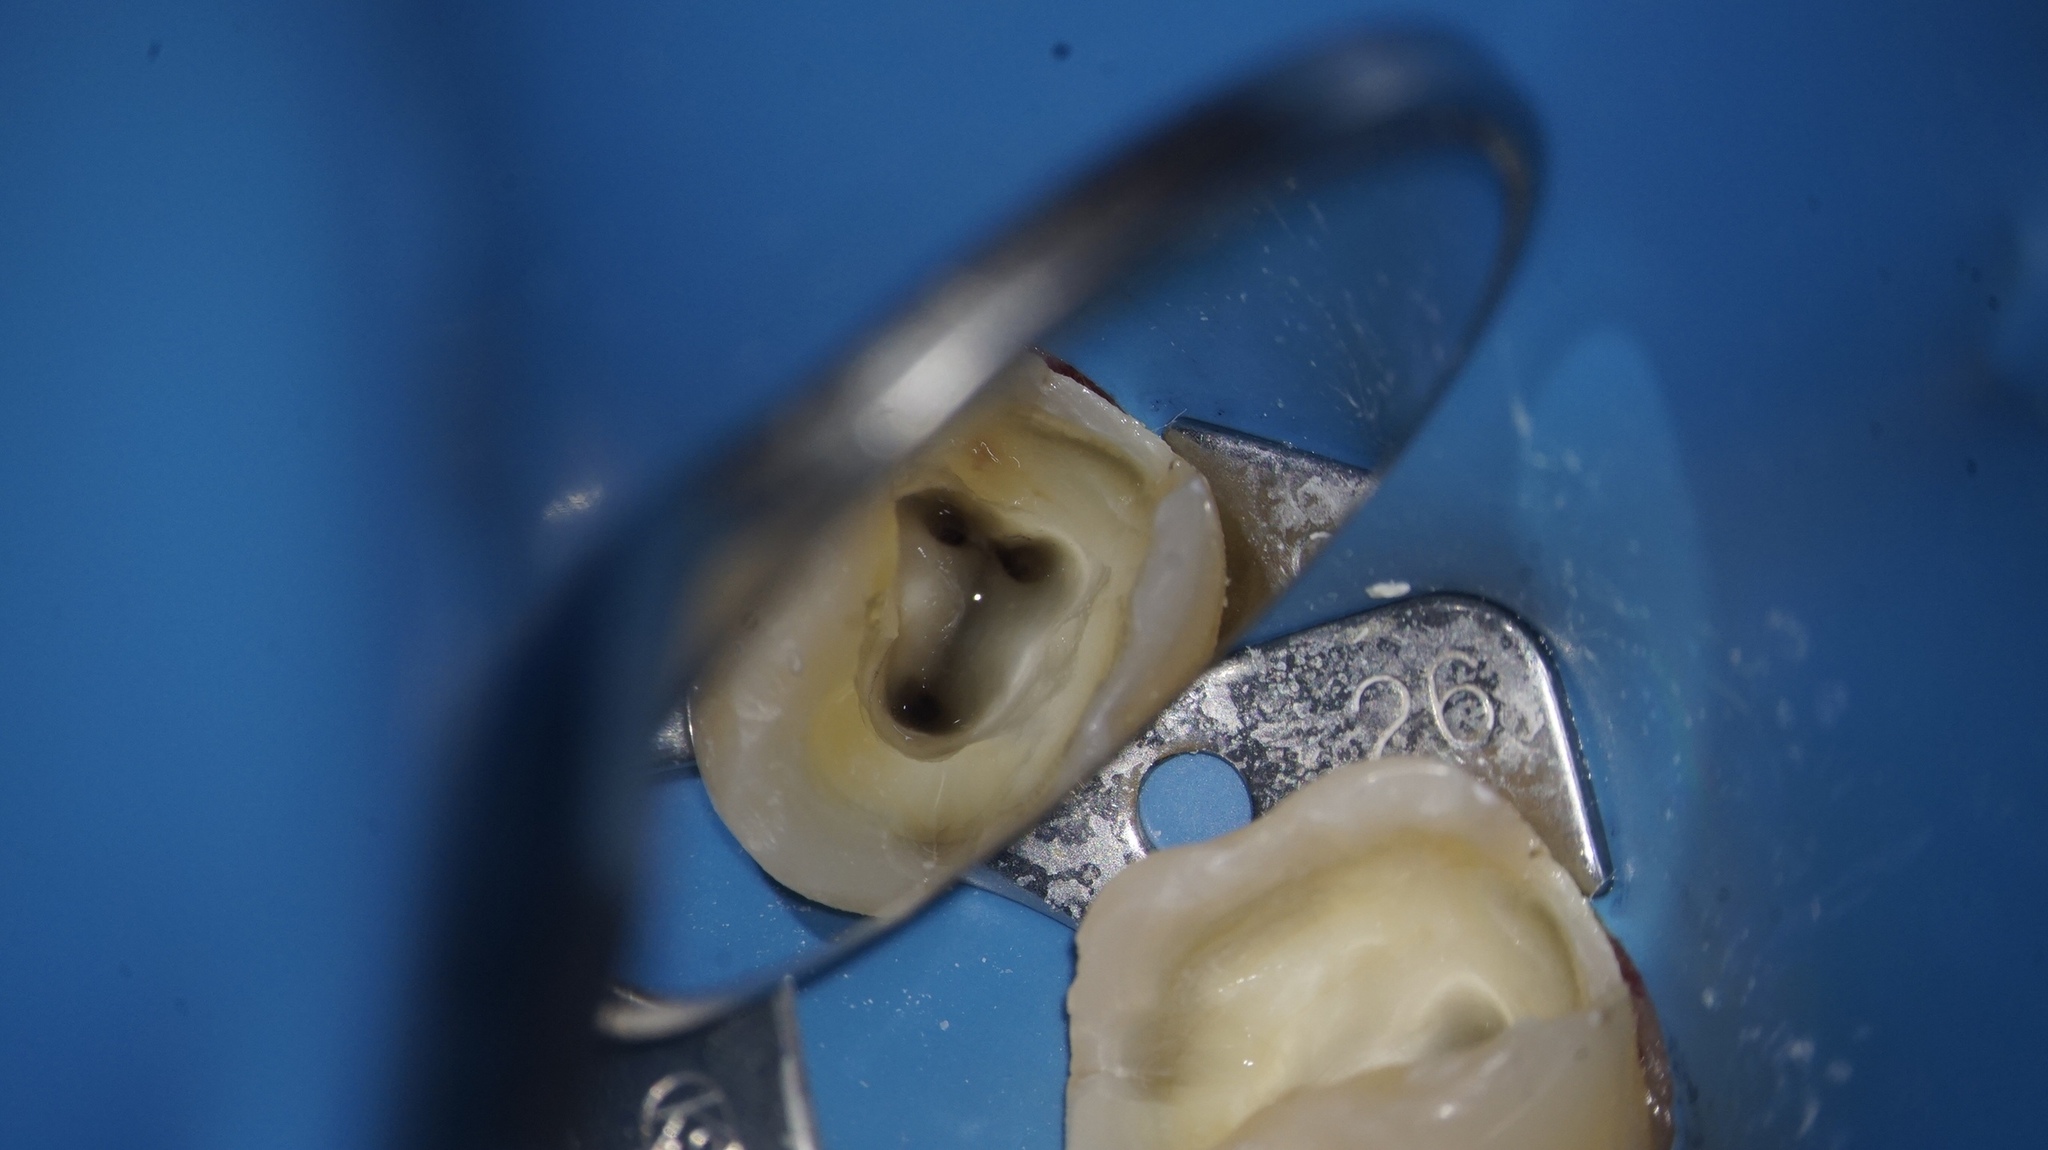

К вопросу о ВСЕХ каналах. Это зуб до вмешательства. Видим 3 канала, ранее лечены, пломбированы гуттаперчей. А на самом деле каналов 5 (фото ниже). Черные отверстия - это устья корневых каналов, т.е. место их начала.